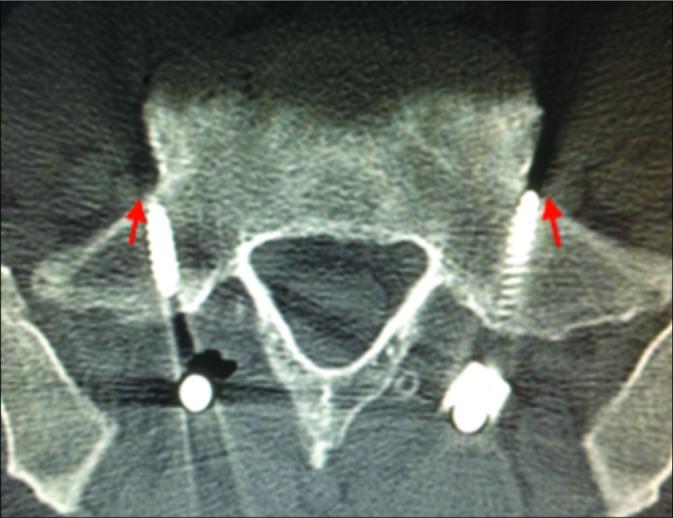

tEMG, somatosensory-evoked potential (SSEP), and transcranial electrical motor-evoked potential (TcMEP) data were retrospectively reviewed from 2015 to 2017 during open posterior lumbosacral instrumented fusions. We utilized screw stimulation alert thresholds of <14 mA (tEMG) and recorded from the lower extremity muscles and anal sphincter. Furthermore, all patients underwent routine postoperative computed tomography (CT) scans to confirm the screw location.

There were 106 S1 screws placed in 54 patients: 52 bilateral and 2 unilateral. In 6 patients (11.1%), 7 screws (6.6%) registered at low tEMG thresholds. In 1 patient, the postoperative CT scan documented external malposition of the screw despite no intraoperative IOM/tEMG alert. When S1 misplaced screws were stimulated, the most sensitive muscle was the tibialis anterior; the sensitivity of the IOM/tEMG was 87.5%, the specificity was 97.9%, the positive predictive value was 77.8%, and the negative predictive value was 98.9%. TcMEP and SSEP did not change during any of the operations. Notably, no patient developed a new neurological deficit.

Anterolateral S1 screw malposition can be detected accurately utilizing IOM/tEMG stimulation of screws. When alerts occur, they can largely be corrected by partially backing out the screw (e.g., a few turns) and/ or changing the screw trajectory.